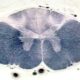

El tálamo es una estructura cerebral situada en el diencéfalo, que es una de las principales divisiones del encéfalo. Se considera el conjunto de núcleos más importante del diencéfalo debido a su función fundamental en el procesamiento y distribución de información sensorial hacia la corteza cerebral.

La anatomía del tálamo también es importante para comprender su función. Los dos tálamos, derecho e izquierdo, están separados medialmente por el tercer ventrículo, que es una estructura llena de líquido cefalorraquídeo que se encuentra en el centro del cerebro. Lateralmente, el tálamo está separado del núcleo lenticular por la cápsula interna, que es una banda de fibras nerviosas que conecta el cerebro medio y la corteza cerebral. Posteriormente, el tálamo se relaciona con el atrio, una cavidad en el cerebro, mientras que anteriormente se relaciona con la cabeza del núcleo caudado y el fórnix, una estructura en forma de arco involucrada en la memoria. Por debajo, el tálamo se conecta con el hipotálamo, una estructura clave en la regulación de funciones corporales, la región subtalámica y el mesencéfalo, que es la parte del tronco encefálico responsable de diversas funciones sensoriales y motoras.